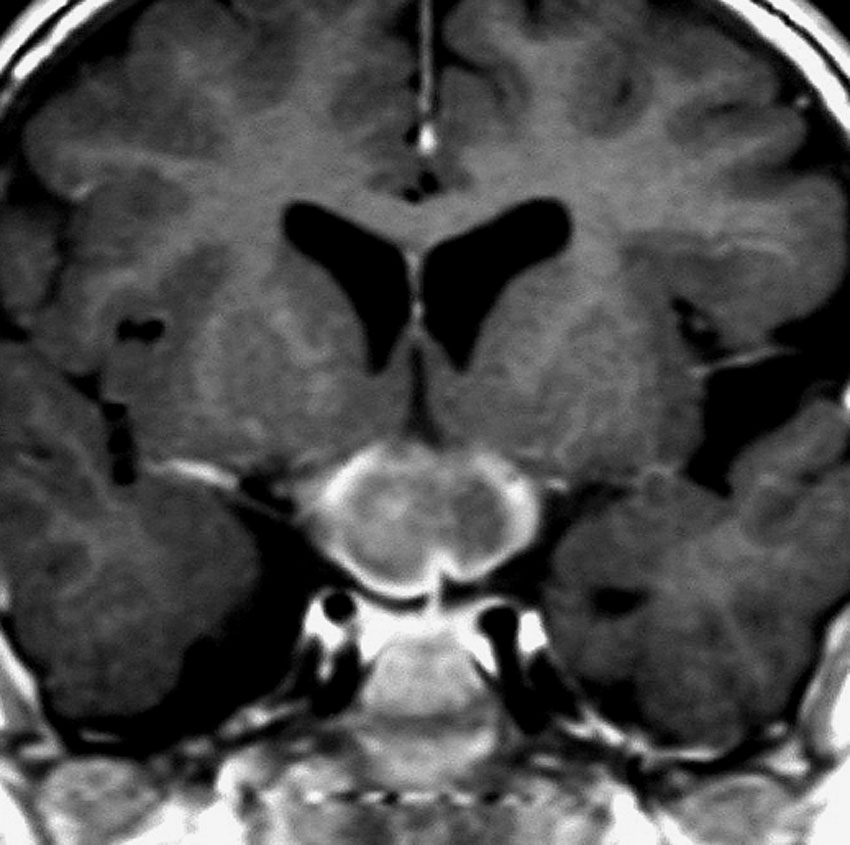

whole optic pathway pilocytic astrocytomaとは

両側の眼窩内視神経から視交叉、視索,外側膝状体,内包後脚,視放線近位部までが腫瘍化しています。FLAIRで高信号で,不規則にガドリニウム増強されます。これを手術摘出したり生検したりしても無駄です。放射線治療は不可能であり治療方法は化学療法のみです。

この子はCDDP/VCRの化学療法から開始して12年になりますが,今は無治療でわずかな視力ですが学校に通っています。優等生です。自然退縮を見ていますが,今後も変化する可能性はすこし残しています。